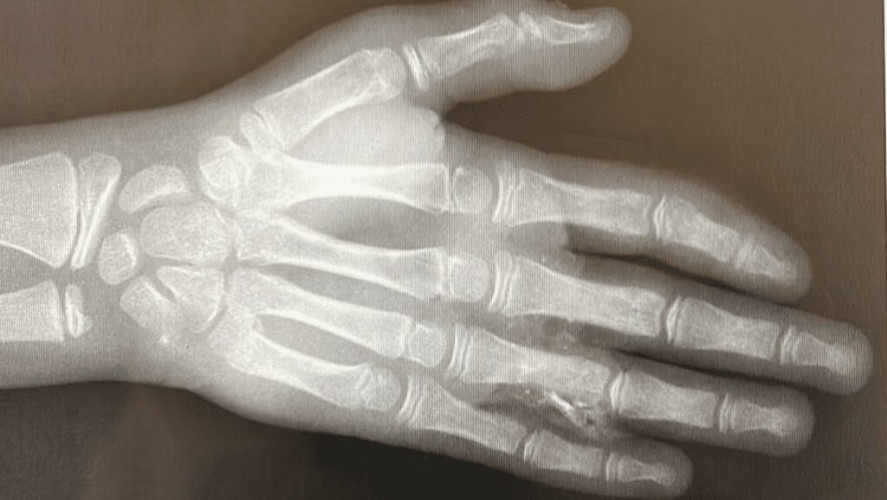

وتفصيلاً، تم نقل المصاب إلى طوارئ المستشفى؛ نتيجة حادث انقلاب بالسيارة أدى إلى تهتك عميق في اليد اليسرى ممتد من راحة اليد حتى أطراف الأصابع، مع كسر مفتوح وتأثر شديد بالدورة الدموية المغذية للأصابع، وبعد عمل الإسعافات الأولية اللازمة قام الفريق الطبي بإجراء تدخل جراحي تم خلاله تنظيف الجرح وإزالة الأنسجة التالفة مع رد مفتوح للكسر، ليتم بعدها نقل المصاب إلى مدينة الملك سعود الطبية لاستكمال العلاج وتقييم الدورة الدموية للأصابع حتى استقرت حالته وغادر المدينة الطبية بعد التأكد من سلامته، ليكمل رحلة علاجه والمتابعة في العيادات الخارجية.